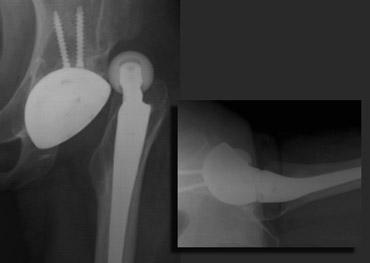

Tràn xi măng ra ngoài

Khi ổ cối được chuẩn bị để đặt cốc, có thể xảy ra thủng. Khiếm khuyết này được lấp đầy bằng mảnh xương, xi măng hoặc ghép xương.

Tràn xi măng ra ngoài thường không có triệu chứng.

Các biến chứng hiếm gặp bao gồm rò ruột, bao bọc các cấu trúc mạch máu thần kinh và bỏng thành bàng quang.